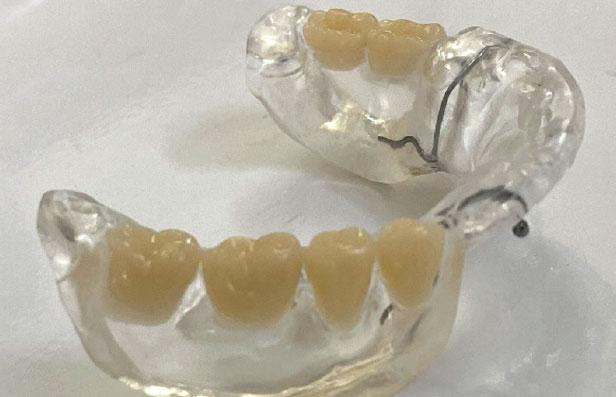

Смоделированы (рис. 11), изготовлены и установлены провизорные коронки из полиметилметакрилата (PMMA) (рис. 12).

Рис. 11. Модель провизорных коронок из полиметилметакрилата

Fig. 11. Polymethyl methacrylate temporary crown model